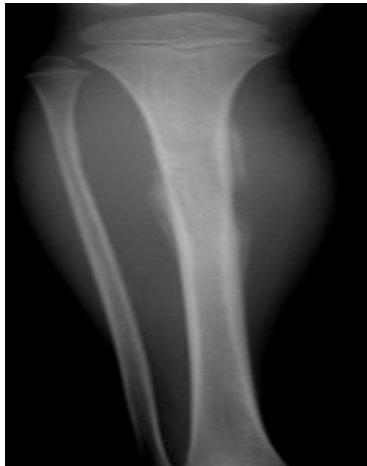

Popcorn, cartilaginous - chondrosarcoma usually - even though theres no perosteal reaction

site: distal femur size: Most (involving how much? / cm?) matrix: mixed - mainly radiopaque , wide zone of transition, cortical destruction, resulted periosteal reaction, and codman’s triangle soft tissue involvement: